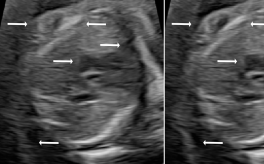

Three in vivo Bmode fetal images with and without aberration correction are presented in Figs. 10-12. GIF images of examples A-L (see Fig. 9 and Table 5) alternating between the corrected and uncorrected images are uploaded as supplementary material. The differences in image quality are easier to appreciate in the GIFs than in a side-by-side comparison. The data points for the three examples are colored black in Fig. 9. Table 5 give tabular values for the global sound speed estimate, sharpness increase (κ𝜅\kappa) and answers from the clinical evaluations.

Figure 11: Example B. In vivo fetal Bmode image using constant 1540 m/stimes1540dividemetersecond1540\text{\,}\mathrm{m}\text{/}\mathrm{s} and the estimated average sound speed map. The average sound speed map is shown in the top right corner and the rightmost colorbar indicates the sound speed values. Alternating GIFs are found in the supplementary material.

The in vivo examples A-C, in Figs. 10-12 respectively, show different nuances of how sound speed aberration correction improves focusing quality. A noticeable improvement in Fig. 10 is the improved contrast and clarity of borders. The sound speed correction seems to remove the double structure indicated by the arrows in Figs. 10c-10d. The skull border and the brain structures in Fig. 11 are also better defined and clearer after aberration correction. Example C in Fig. 12 is the image with the highest increase in Tenengrad κ𝜅\kappa, seen from Fig. 9 and Table 5. The improvement in image quality is evident around the boundary of the fetus body and the correction sharpens the structures indicated by the arrows. The improved contrast between the layers in the shallow tissue layers is also noticeable.